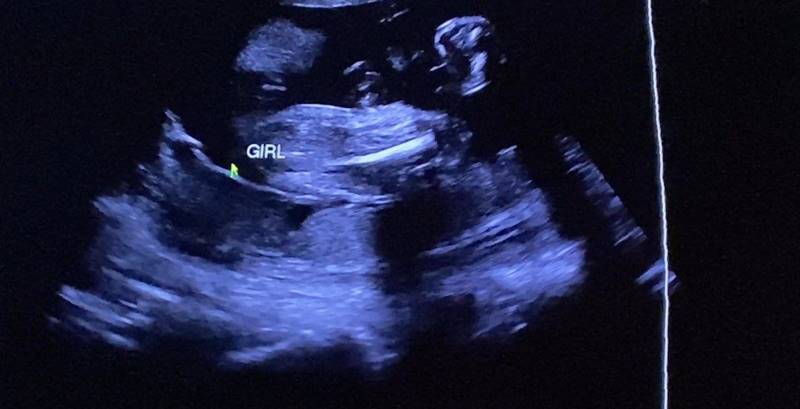

ฟ้า ยงวรี เผยข่าวดีตั้งท้องลูกสาวคนแรก กับคลิปนาทีรู้ว่าตั้งครรภ์ และโมเมนต์อบอุ่นกับสามีชาวต่างชาติ ส่งความรักความผูกพัน ถึงนางฟ้าตัวน้อย